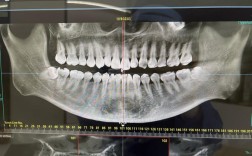

牙齿并非孤立存在,其下方有牙根(牙体组织的主要支撑结构),周围包裹着牙槽骨(固定牙齿的骨骼),拍片(如根尖片、全景片)能清晰显示牙根的形态、长度、是否有弯曲、吸收或断裂,以及牙根间是否存在骨间隔、囊肿或炎症,若患者牙根存在先天弯曲或过短,盲目施加矫正力可能导致牙根吸收甚至牙齿脱落;而埋伏牙(未正常萌出的牙齿)或多生牙(额外生长的牙齿),只有通过拍片才能准确定位其位置和方向,避免矫正中误伤。

牙齿的移动依赖于牙槽骨的改建(压力侧吸收、牵引侧增生),而颌骨的大小、形态直接影响矫正方案的设计,头颅侧位片能测量颌骨的长度、宽度、高度,判断是否存在“地包天”“龅牙”等骨性畸形——若骨性问题突出,可能需要配合正颌手术才能达到理想效果;全景片则可观察牙槽骨的高度和厚度,若牙槽骨因牙周病等原因吸收严重,牙齿移动时可能暴露牙根,甚至引发松动,拍片还能发现颌骨内的囊肿、肿瘤等病变,避免在矫正过程中刺激病灶。

| 全景片(曲面断层片) | 全口牙齿、牙根、牙槽骨、颌骨、上颌窦、下颌神经管等 | 观察牙齿数量、萌出方向、牙根形态,判断牙槽骨高度、有无囊肿/埋伏牙 |

| CBCT(锥形束CT) | 三维重建牙齿、牙根、牙槽骨、神经血管等精细结构 | 精准定位复杂病例(如埋伏牙、种植体植入),评估骨量,降低神经损伤风险 |